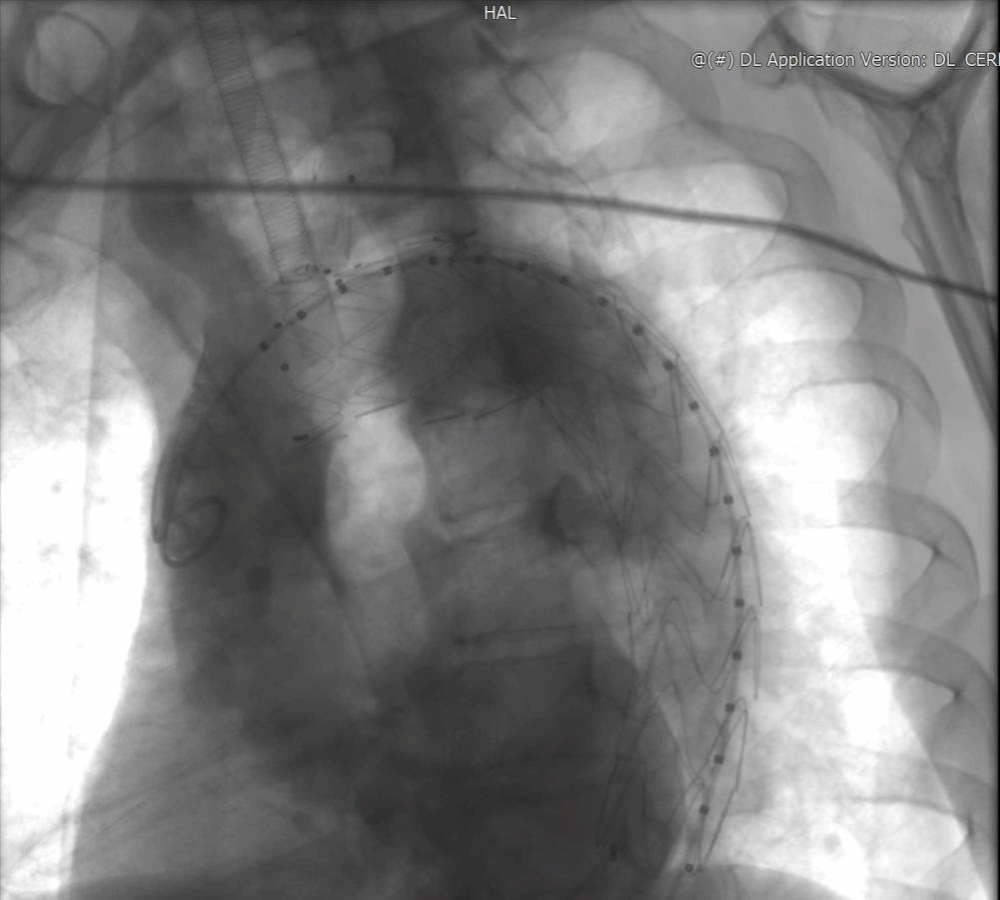

邓捷主任团队反复研判影像后发现,吴大叔的动脉瘤已超出常规 B 型夹层介入范围,若按传统方案,要么牺牲分支血管血供,要么面临 30% 以上的开胸手术并发症风险。“必须为他量身定制方案。” 邓捷主任提出创新思路:Castor 单分支支架锚定左颈总动脉 + 体外开窗重建左锁骨下动脉,既隔绝动脉瘤,又保住脑部与上肢供血。这套方案的关键在 “精准”—— 体外开窗的大小、位置需与血管开口完全匹配,误差超 1 毫米就可能导致内漏或血管闭塞。“邓主任拿着 CTA 图量了又量,连血管夹角都算到小数点后,还加班细化手术流程。” 吴大叔后来从护士口中得知,为确保万无一失,团队还专门调取了国内外 20 余例类似手术文献进行参考。

吴大叔回忆,术前多学科会诊(MDT)时,麻醉、心外、血管外、重症医学科专家逐一敲定细节:从术前评估到应急手术预案,甚至细化到导丝通过血管的路径。手术当天,邓捷主任带领刘小军、韩婕、张恒医生团队身着 30 斤铅衣,在 DSA 设备引导下精准操作:先将定制支架接入左颈总动脉,再以支架为 “坐标” 体外开窗,最后植入左锁骨下动脉支架。“最紧张的是造影那一刻,看到血管通了、瘤子被隔绝,大家才松了口气。” 主治医师刘小军说,整场手术耗时 2 小时,全程无大出血、无血管损伤。术后第 2天,吴大叔就能自主活动肢体;术后第三天,各项指标正常,顺利出院。“原以为要躺半个月,现在能买菜做饭,跟没生病一样!” 出院时,他特意给邓捷主任团队鞠了一躬。